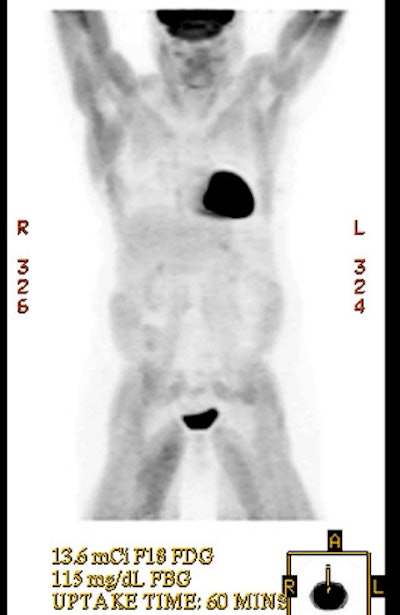

Hyperinsulinemia: The patient below had

a normal glucose level and was injected for an FDG PET

scan. Imaging revealed intense cardiac uptake and a large

about of muscular activity. The findings are consistent

with a hyperinsulinemic state and the patient subsequently

admitted to eating a small breakfast. |